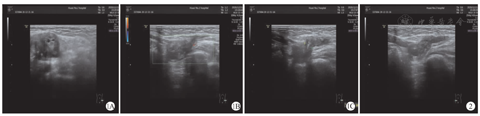

患儿1入院时双侧腹股沟彩色多普勒超声检查结果显示:左侧腹股沟查见不均质弱回声团块,大小约为2.3 cm×1.4 cm×2.2 cm,其内可见卵巢样回声,向上疝入腹腔,疝入腹腔入口宽度约为0.7 cm,团块内探及血流信号。右侧腹股沟区查见不均质弱回声团团块,大小约为1.6 cm×1.0 cm×1.4 cm,可见团块蠕动,向上疝入腹腔,疝入腹腔入口宽度约为0.8 cm,团块内探及血流信号。对患儿1的超声诊断为左侧腹股沟疝(疝内容物为卵巢及肠管)与右侧腹股沟疝(疝内容物为肠管)。患儿1左、右侧腹股沟彩色多普勒超声检查结果,分别见图1、图2。